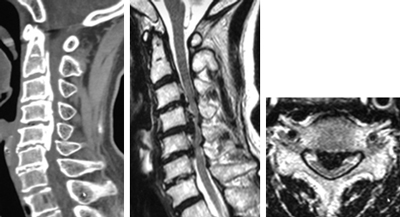

後縦靱帯骨化症、黄色靱帯骨化症

せぼね(脊椎)は7個の頚椎、12個の胸椎、5個の腰椎と仙椎から構成されます。腰椎は主に5つの骨と、間にあるクッションのような椎間板、また神経組織が通っている脊柱管から成り立っています。後縦靱帯骨化症は椎体の後面で脊髄の前にある後縦靱帯が骨化する病気で、黄色靭帯骨化症は脊髄の後ろにある黄色靭帯が骨化する病気で、頚椎が最も発症頻度が高いですが、胸椎や腰椎にも起こり得ます。いずれも根本的な治療法がないことから、厚生労働省難治性疾患克服研究事業の対象疾患に指定されています。白人に比べて東アジアや日本人に多く、頚椎後縦靱帯骨化症は本邦で約3%、男女比はおおよそ2:1ですが、全身性の骨化では女性に多いことが知られています。家族内発症もあることから遺伝的関与の可能性、そのほか肥満や糖尿病との関連も指摘されています。

後縦靱帯の骨化や黄色靭帯の骨化があるからといって、必ずしも神経障害が出るわけではありません。但し、骨化のタイプや大きさによっては、発症や進行をしやすいことがあり、特に転倒による急激な悪化には注意が必要です。局所の症状として、頚部や背部の痛み、また肩こりなどの症状が生じます。脊髄が障害されると、手指の巧緻運動障害(箸が持ちづらい、字が書きづらい、ボタンが上手くはめられない)、痙性歩行(ふらつき・つまずきやすい・歩行がぎこちない)、膀胱直腸障害(頻尿・残尿感)などの症状が生じます。

骨化のタイプや大きさ、不安定性の有無、脊髄の圧迫具合、またせぼね全体のバランスなどを見るためにX線検査やCT検査、MRI検査などを行います。進行例では脊柱管の狭さをより詳しく評価するために入院して脊髄造影検査を行う場合があります。成人期では血管性のしびれがないか評価するために両手足の血圧を測ったり、骨粗鬆症の有無を評価するために骨密度検査を行うこともあります。